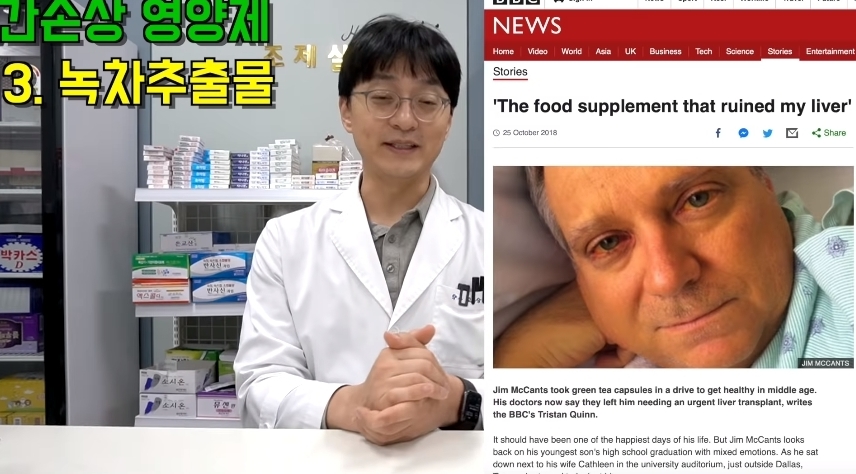

그러나 한번만 먹어도 간이 망가질 수 있다는 영양제들에 대한 글이 온라인 커뮤니티에 올라와 누리꾼들 사이에서 엄청나게 화제가 되고 있다.

해당 게시물에는 먹으면 오히려 몸에 안좋은 영양제들이 올라왔다.